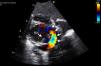

Case 2A two-month-old infant with poor weight gain and a systolic murmur was referred for cardiac evaluation. On examination he was in moderate respiratory distress and cyanotic, with minimal response to supplementary oxygen. A grade II/VI ULS systolic murmur was present. The echocardiogram revealed a small left atrium, dilated right chambers and pulmonary trunk, and a small ASD with a right-to-left shunt. A retroatrial conduit emptying into the coronary sinus was also evident (Figure 1). These findings were suggestive of a cardiac type TAPVR.